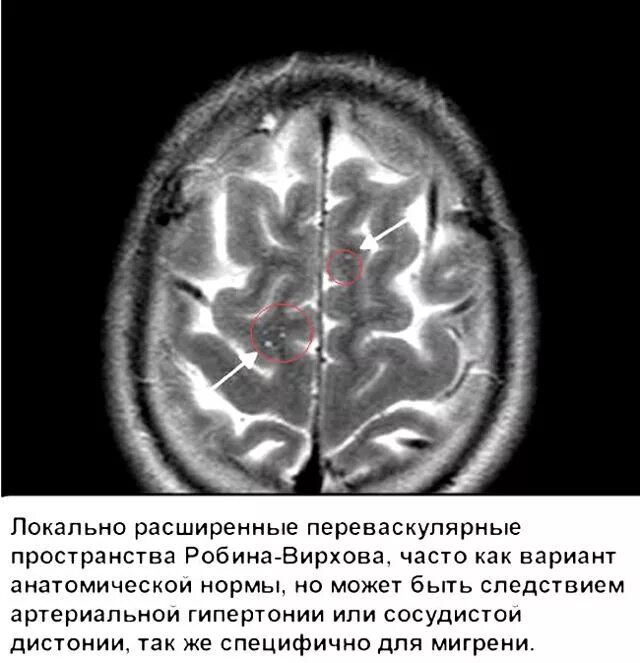

Что значит расширенные периваскулярные пространства